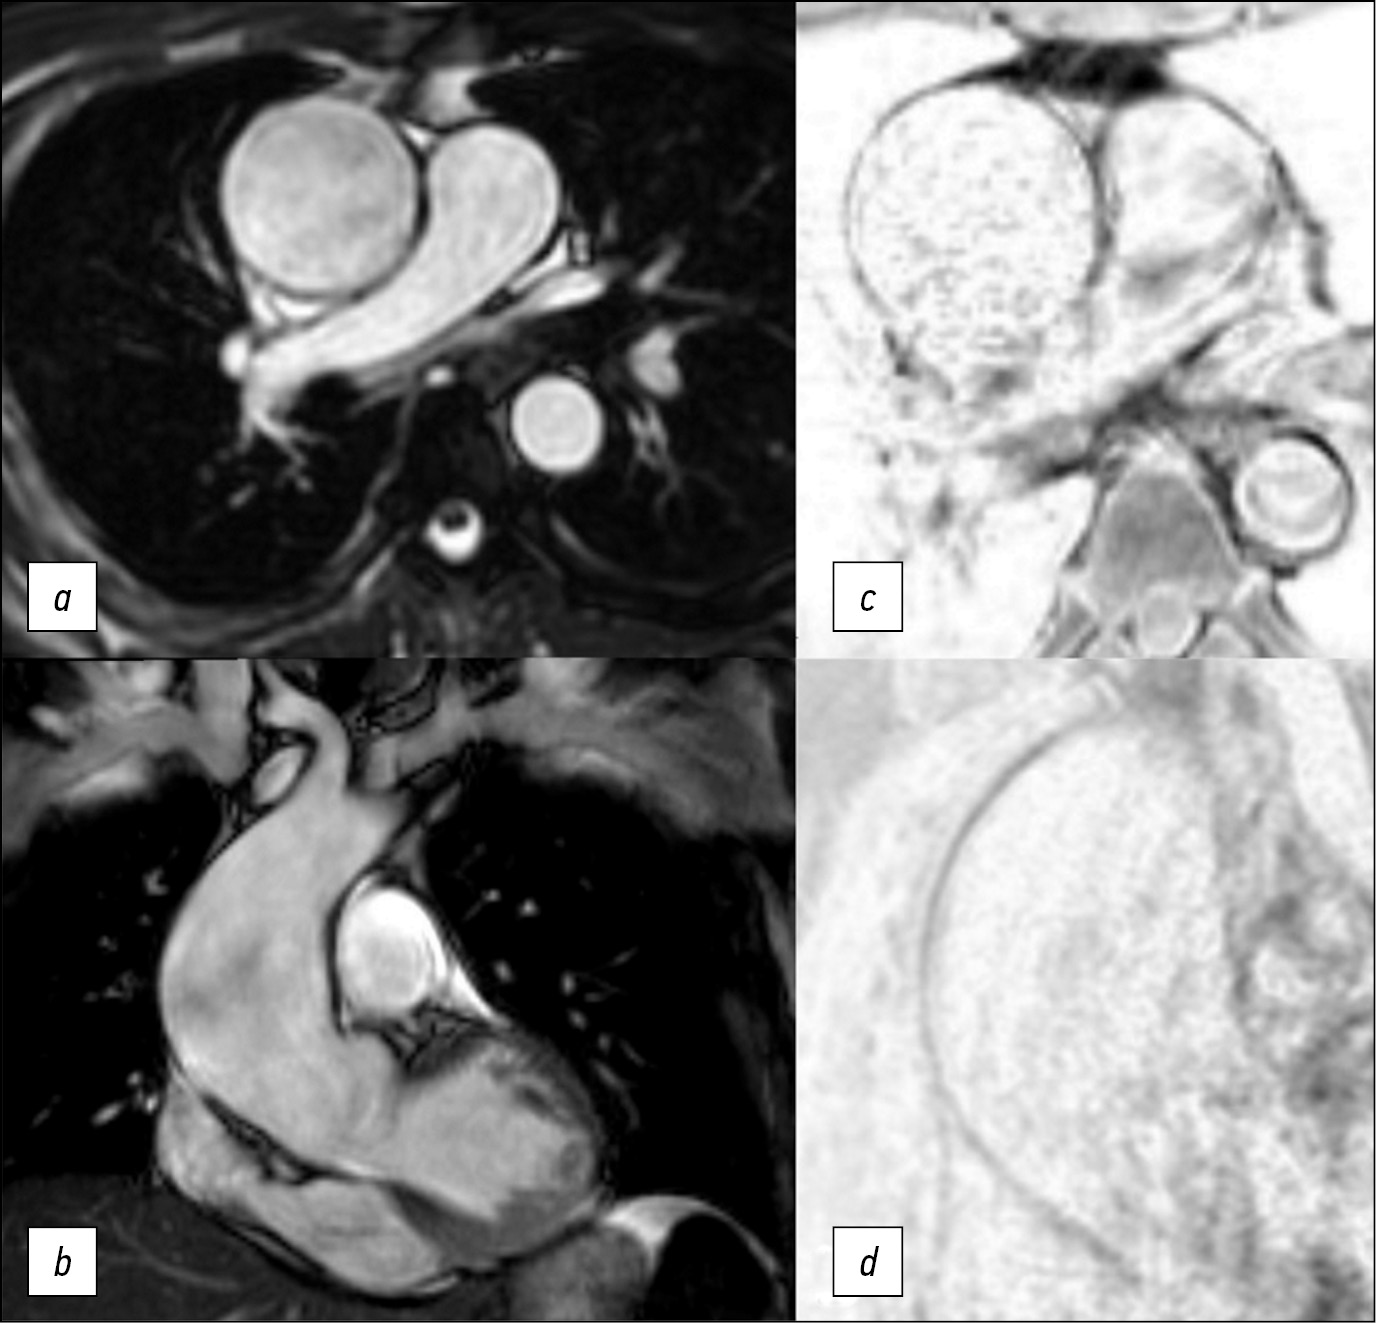

Here we report a case of technological innovation: the use of magnetic resonance imaging to determine surgical strategy.

Here is a 47-year-old man who underwent an magnetic resonance imaging and subsequent surgical treatment of the aortic aneurysm. Unlike echocardiography, magnetic resonance imaging enabled us to view the entire thoracic aorta. Unlike computer tomography, magnetic resonance imaging enabled us to detect changes in the aortic wall accurately. Thus, in this case, the use of magnetic resonance imaging allowed us to determine the distal resection edge. The patient`s postoperative course was unremarkable. Use of electrocardiogram-synchronized magnetic resonance imaging of thoracic aorta allows detecting structural changes of the aortic wall and its mechanical properties. It is significant that magnetic resonance imaging results of the aortic wall correlate with histologic examination.